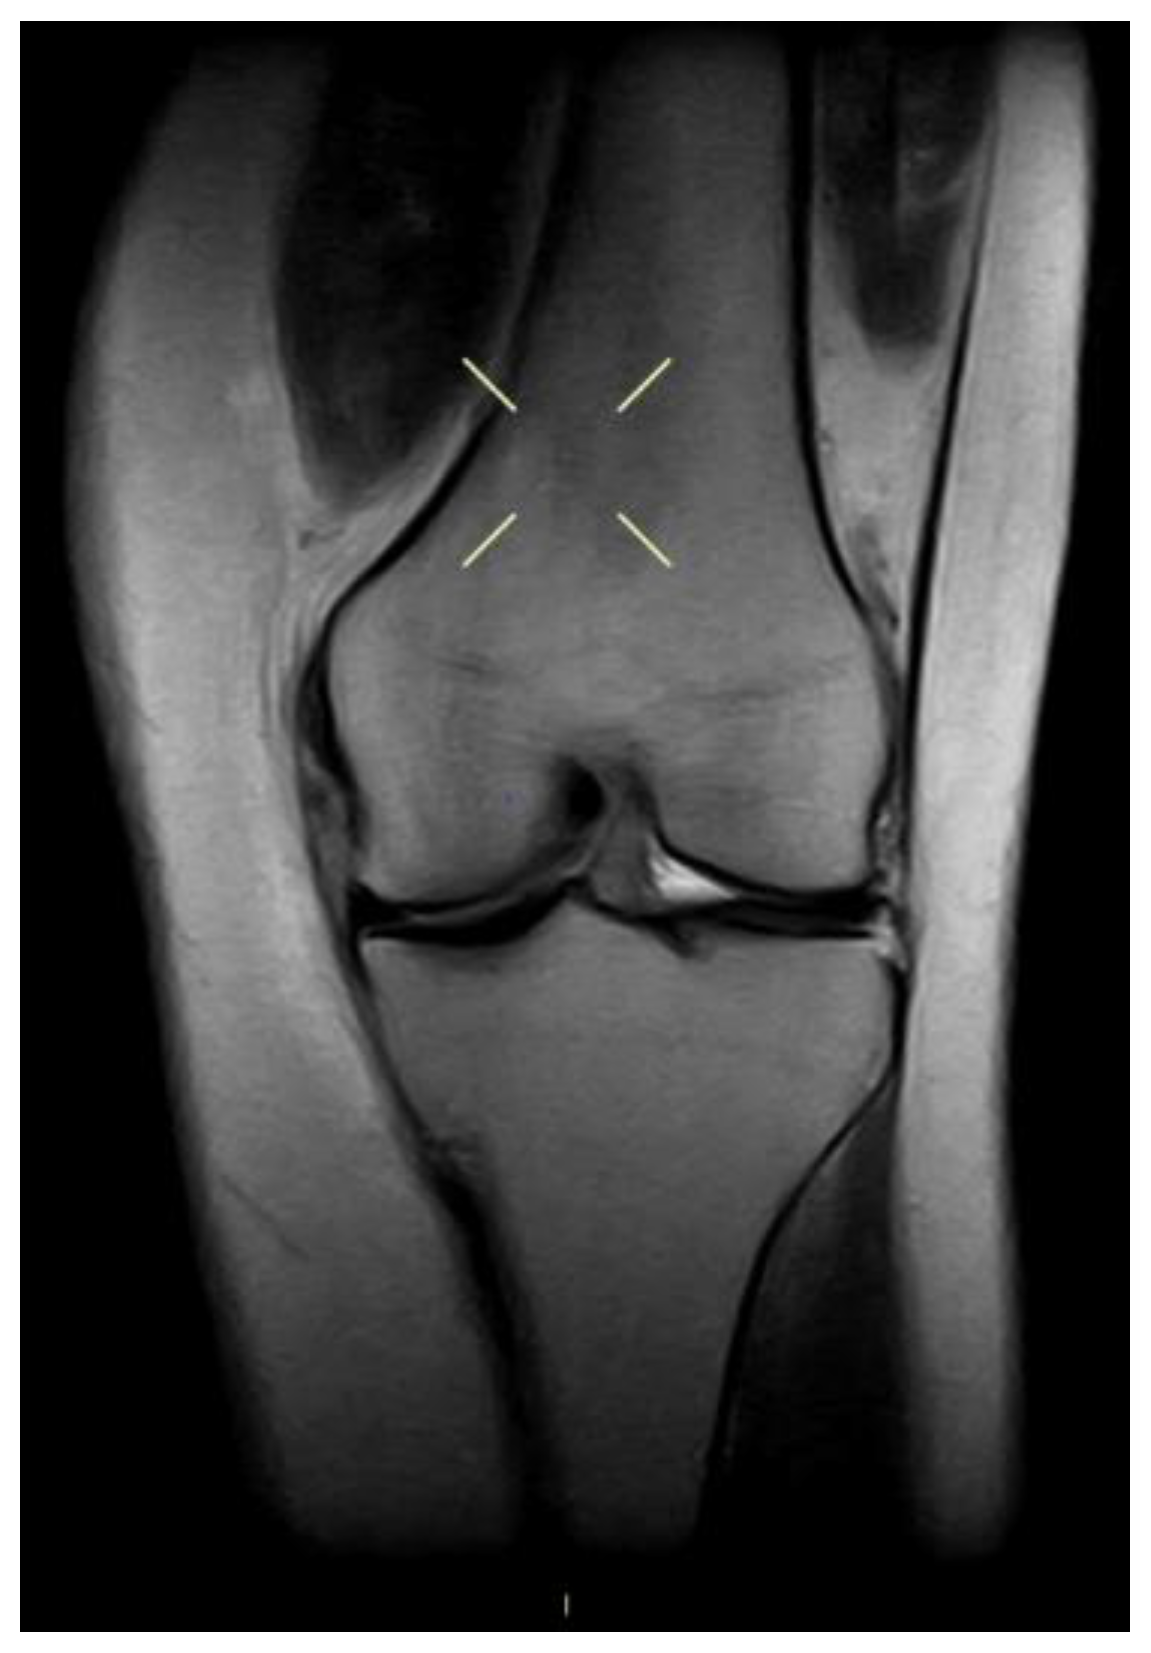

4.4. Magnetic Resonance Imaging (MRI) in the Diagnosis of ACL and MCL Injuries